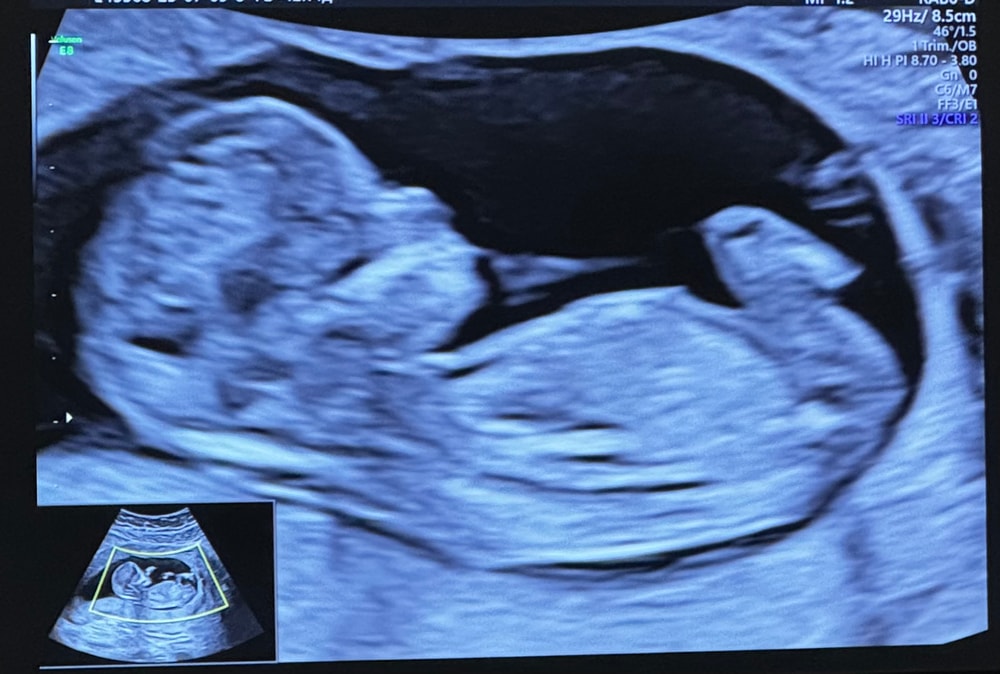

Сегодня провели первый скрининг, можно ли предположить по фото какого пола малыш?) понимаю, что рано, но ужасно любопытно